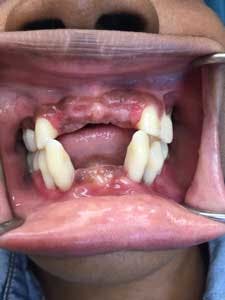

In the next year, the patient described discomfort with tooth No. 5 and generally presented with swollen appearance to the gingiva. Amoxicillin and metronidazole was prescribed to help reduce infection and swollen tissues. The patient was advised to practice safe sex, using protection while taking the antibiotic cocktail. Teeth Nos. 7, 8, 9, and 10 were scheduled to be removed, and a maxillary temporary partial was fabricated for tooth replacement.

Upon returning for the above tooth removal, tooth No. 5 self-avulsed and the other teeth were removed and a temporary partial placed (figures 4 and 5).